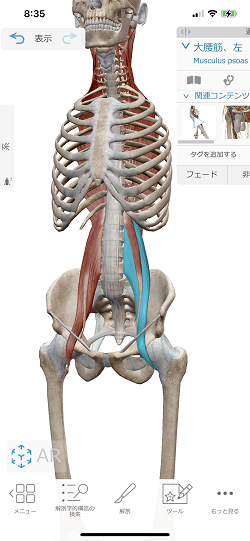

関係する筋肉は『横隔膜』『小腰筋』『大腰筋』です。

大腰筋

小腰筋は約60%の人に存在しない為、大腰筋と合わせて『腸腰筋』と呼んでいますが、これが腰の痛みの原因になっている方が多いのです。

横隔膜は肋骨下縁にドーム状に付着している膜のような筋肉ですが、背骨で腸腰筋とくっ付いていることもあり、横隔膜と同じように腸腰筋も緊張してしまい、腰への負担が増えるのです。

座っている状態は、腸腰筋が短縮して固くなってしまうので、更に腰への負担が増えます。